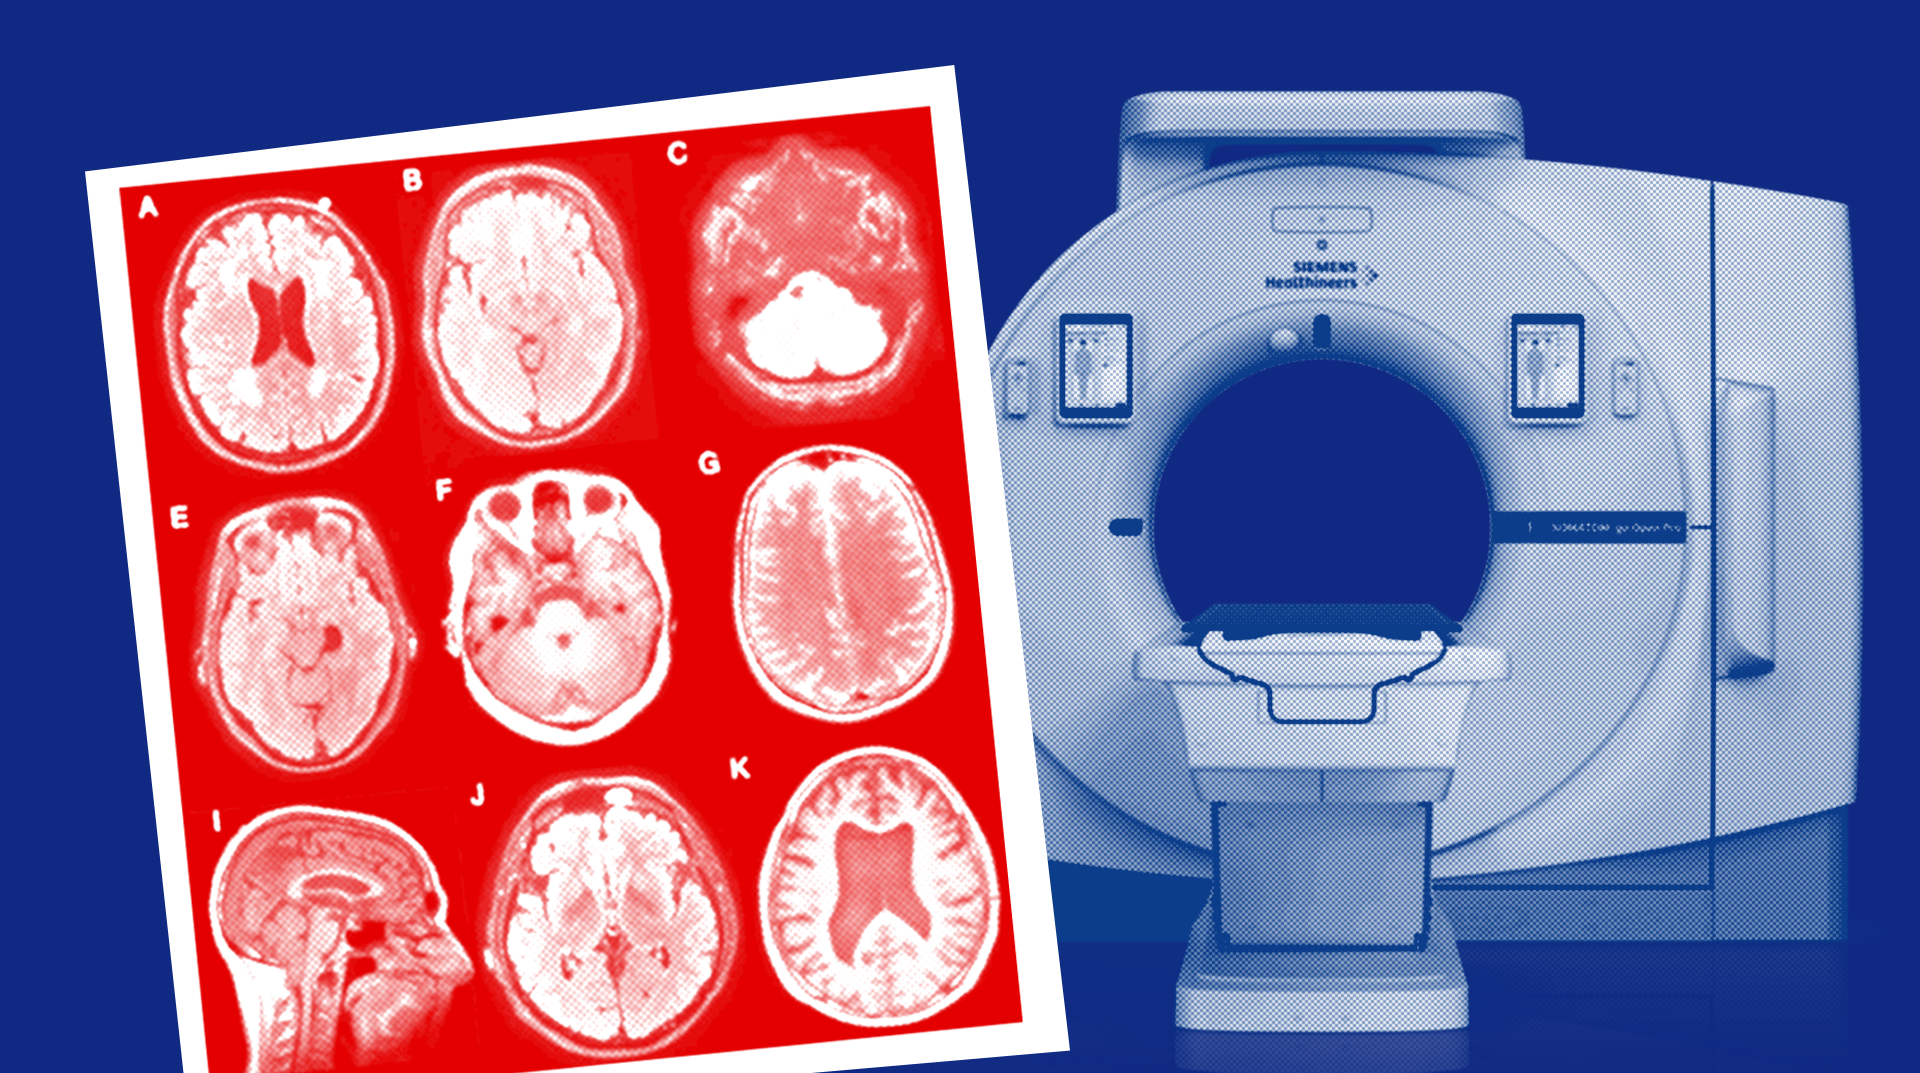

КТ и МРТ: в чем разница методов, какой из них лучше

Сравниваем методы медицинской диагностики — КТ и МРТ. Статья поможет разобраться, как проходят исследования, почему аппараты по-разному визуализируют органы, а также какой метод и в каком случае дает более достоверную информацию.

Все о компьютерной томографии: назначение, виды, результаты

Узнайте, как работает компьютерный томограф, какие виды томографии бывают и чем они отличаются. Рассказываем про СКТ, МСКТ, ПЭТ, ОФЭКТ-КТ и конусно-лучевую КТ.